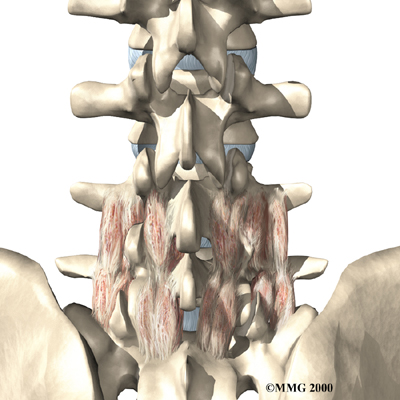

X-rays are of minor help in diagnosing disc herniations. The discs don't actually show up on X-rays. However, doctors can tell if the space between the vertebrae is smaller than normal. This can be an indication that wear and tear on one or more discs is causing problems. However, many peoples' X-rays show degeneration of the discs. This is because degeneration in the discs is part of aging, like skin that wrinkles with time.

X-rays